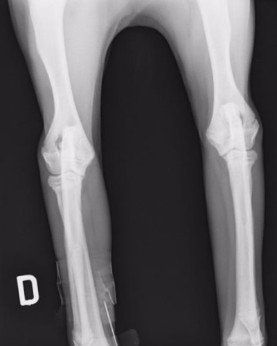

Displasia del gomito e neurologia veterinaria

Oltre all’anca, la nostra clinica si occupa anche della displasia del gomito, una patologia multifattoriale che colpisce spesso le razze di taglia grande. Essa può derivare da:

- frammentazione del processo coronoideo (FCP);

- mancata unione del processo anconeo (UAP);

- osteocondrite dissecante (OCD);

- incongruenza articolare (INC).